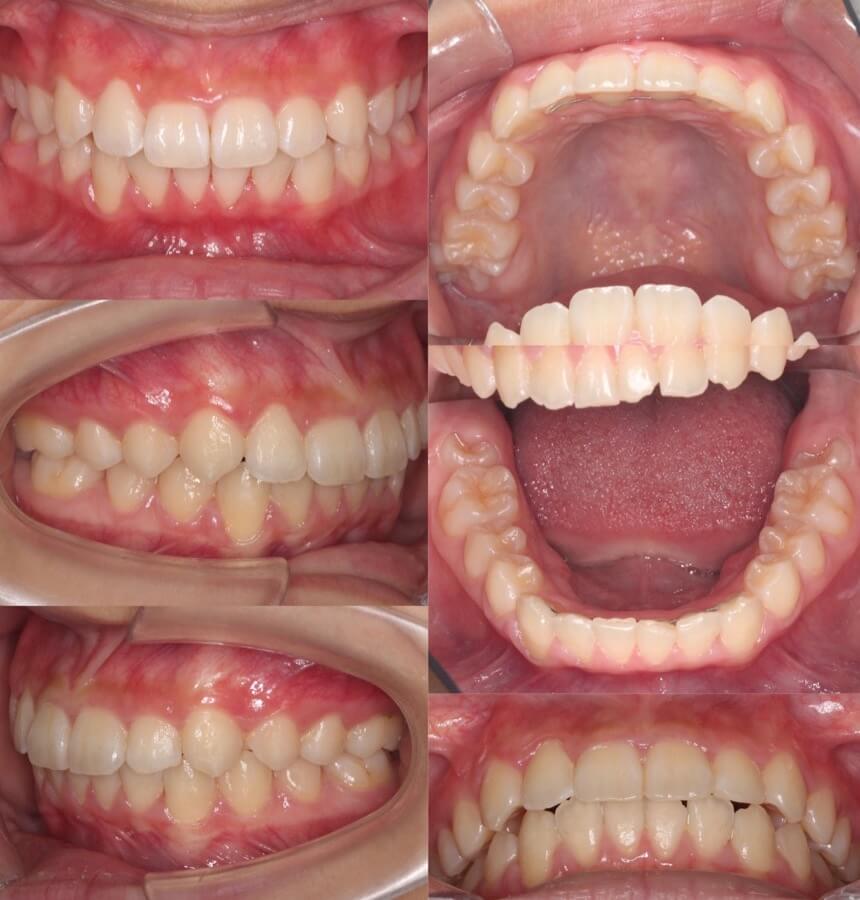

20代女性・マウスピース型矯正

<顔のビフォーアフター>

<症例概要>

主訴:八重歯

年齢・性別:20代女性

住まい:千葉県八千代市

症状:過蓋咬合・叢生・左側上下第二大臼歯欠損

治療方針:上顎前歯圧下・上顎遠心移動・ストリッピング

治療装置:商品マウスピース型矯正装置(アライナー装置)

固定装置:歯科矯正用アンカースクリュー(上前歯x2)

治療期間:1年7か月

アライナー枚数:56+25

リテーナー:上下クリアタイプ+フィックスタイプ

治療費用:990,000(税込)

代表的副作用:痛み・治療後の後戻り・歯根吸収・歯髄壊死・歯肉退縮

▶︎その他の副作用

※マウスピース型カスタムメイド矯正歯科装置は完成物薬機法対象外の矯正装置であり、医薬品副作用被害救済制度の対象とはならない可能性があります。

上の前歯が内側に倒れている事で前歯の噛み合わせが深い状態になっているケースです。歯科矯正用アンカースクリューを使用する事で正しい噛み合わせに、安全に短期間でもっていく事ができました。